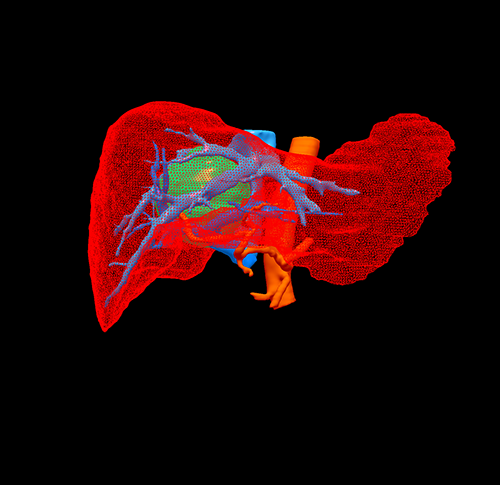

右肝肿瘤---右半肝切除